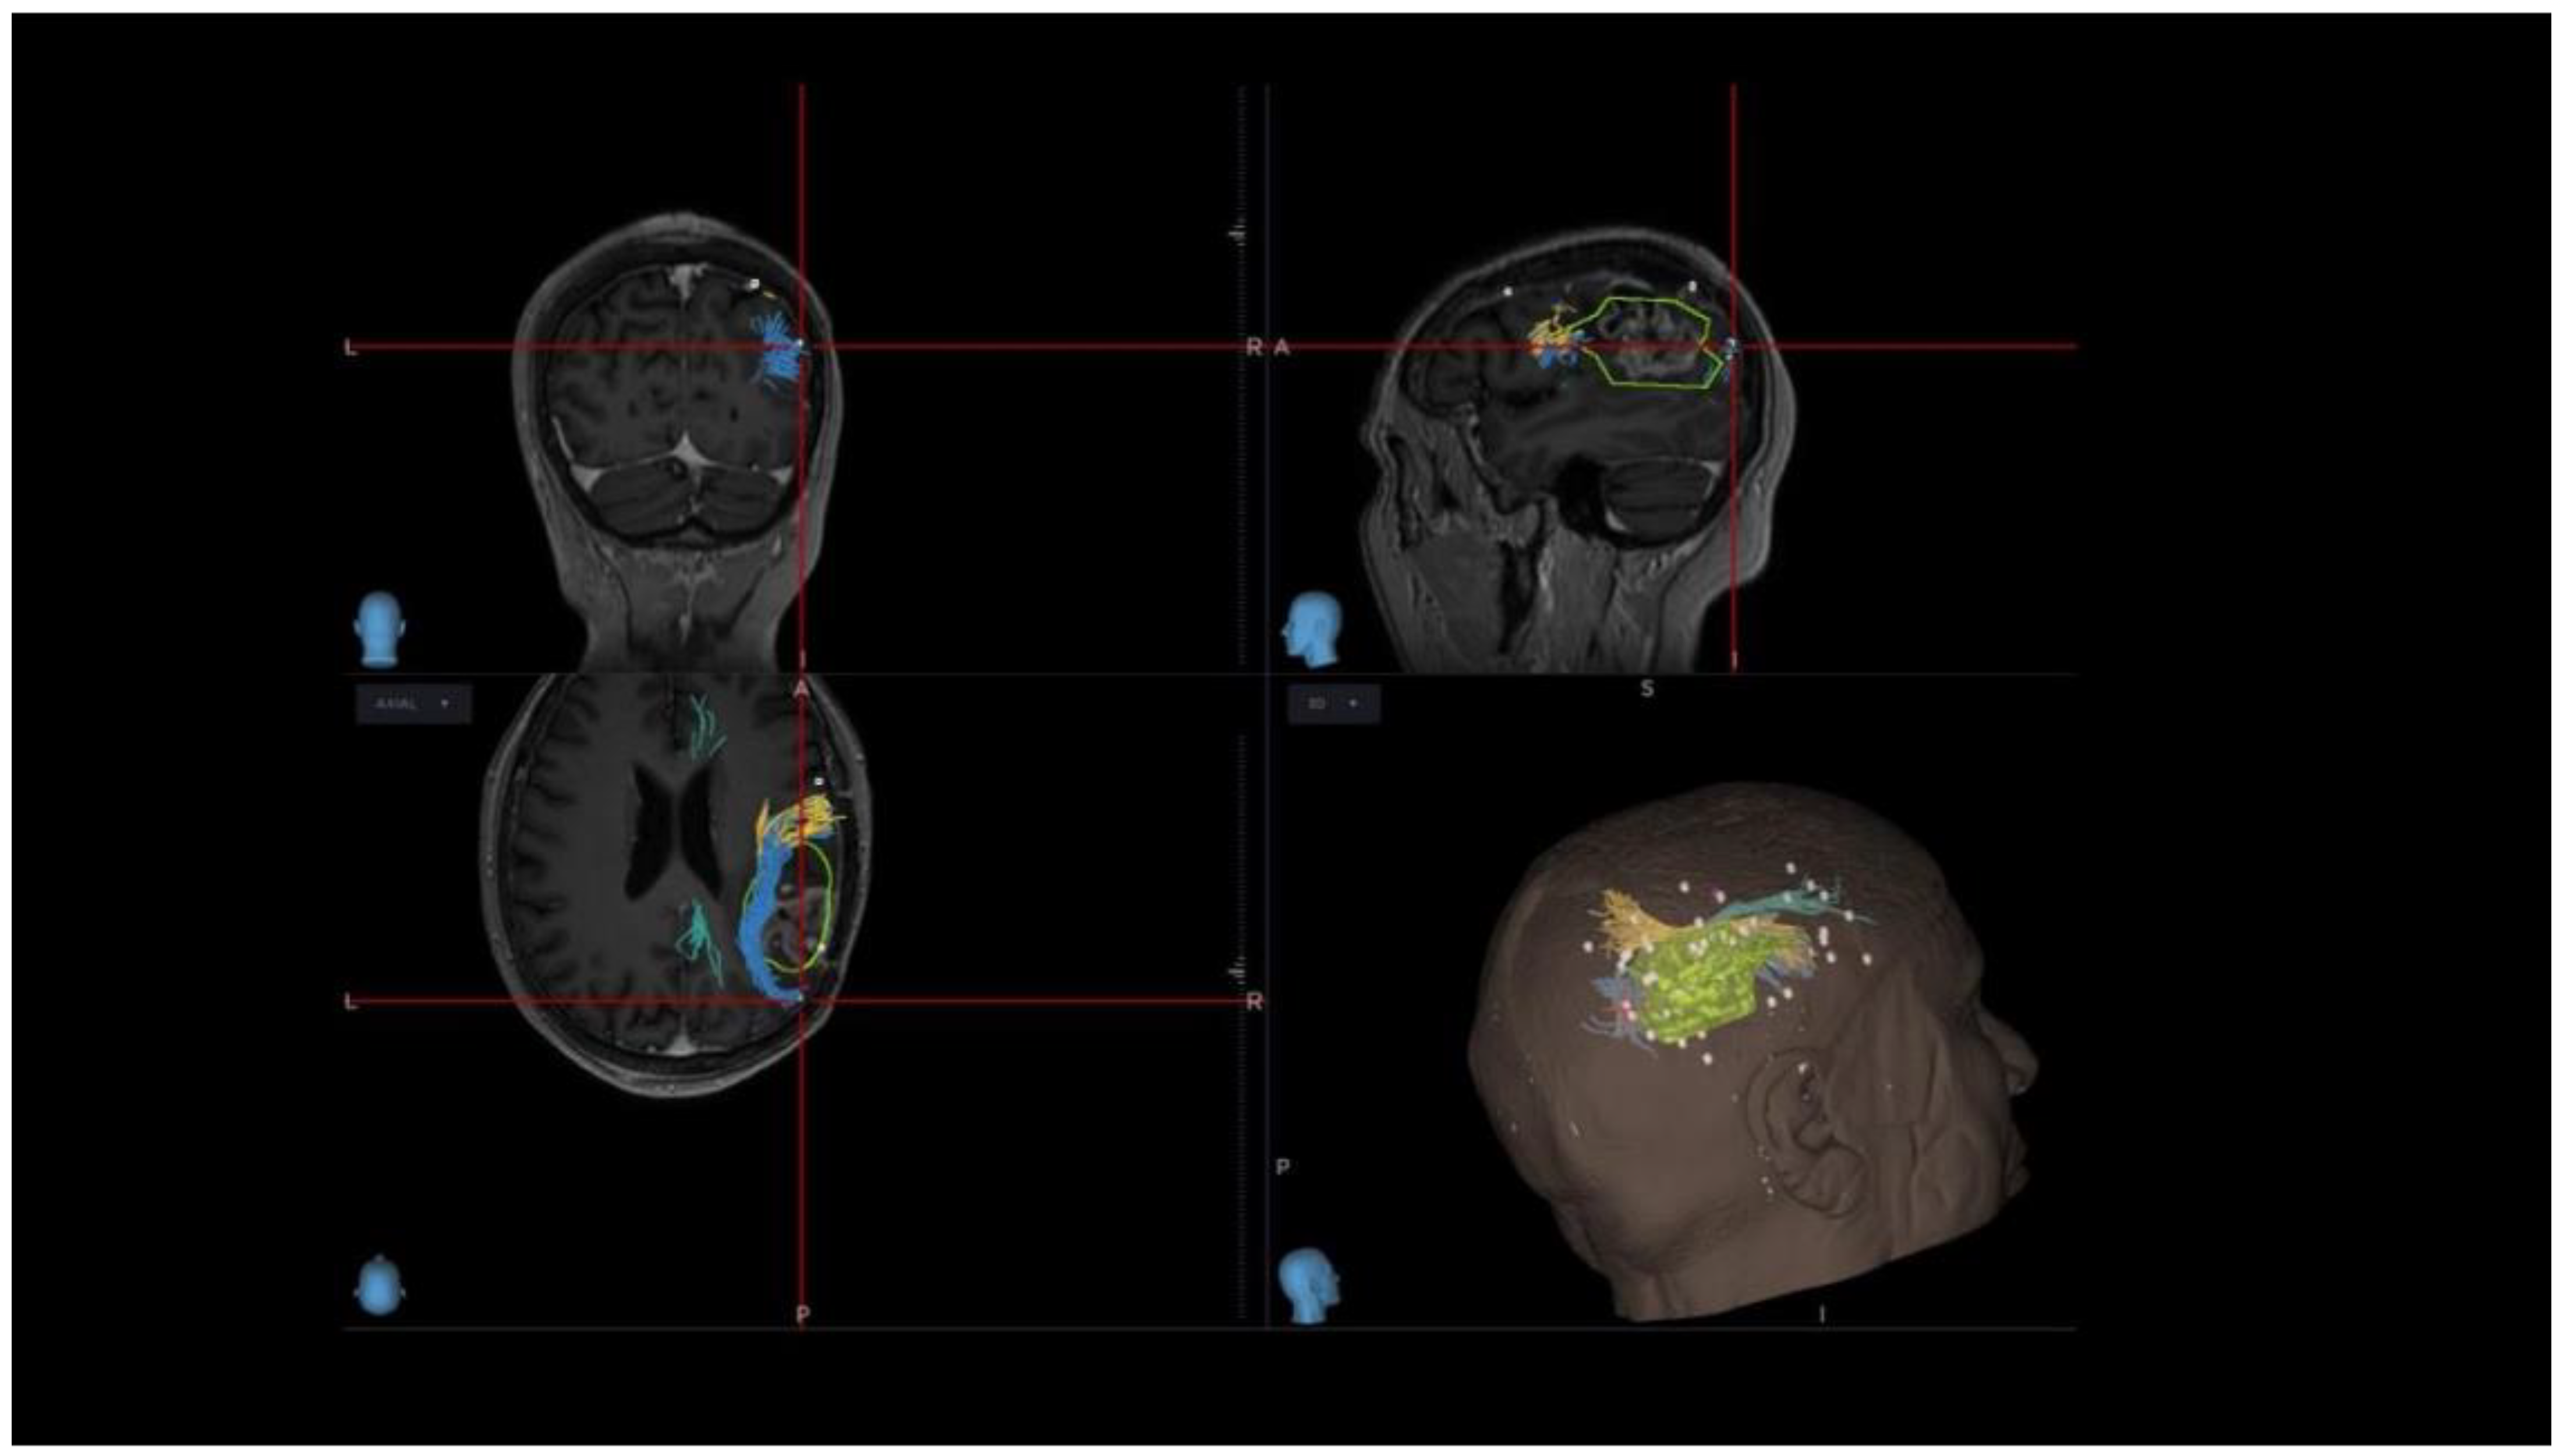

3.2. VS Network: nTMS-Based Tractography and nTMS Mapping

4.4. nrTMS Mapping and DTI Tractography